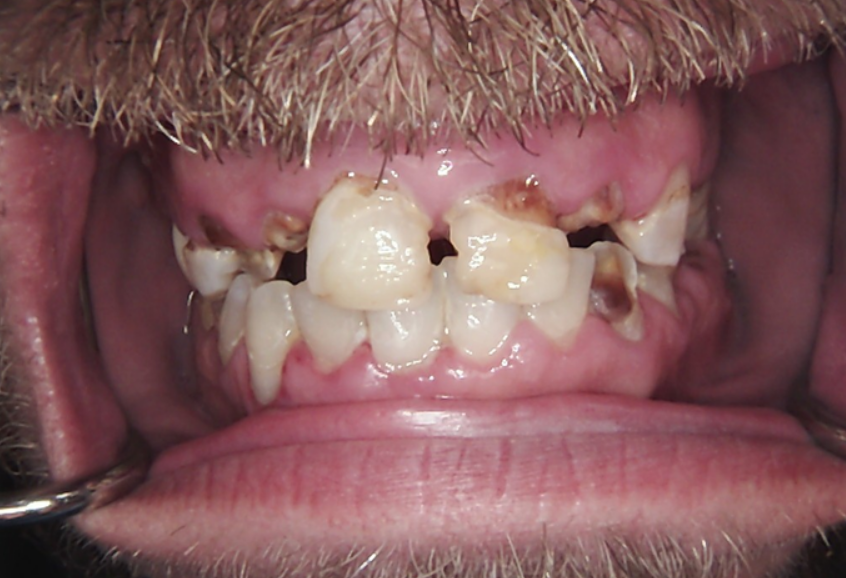

Long-term psychoactive substance use had caused severe xerostomia, contributing to the rapid development of dental caries and decay. The teeth in the upper jaw were non-restorable, and many were already missing. The condition of the lower jaw was slightly better: the anterior teeth were in satisfactory condition, but the posterior teeth were severely decayed and required extraction.

The presented images show the patient’s initial dental condition.